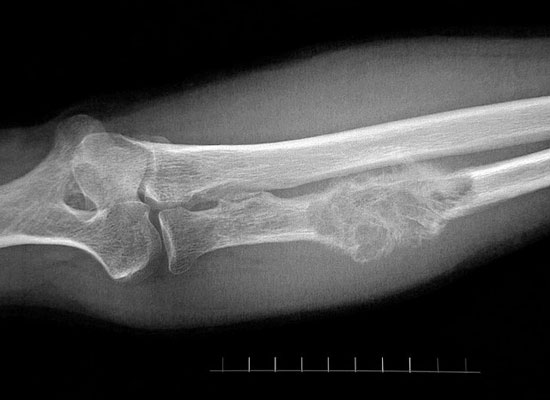

۶- انسانها ۱۲۰ هزار سال است که با تومورهای استخوانی دست و پنجه نرم میکنند

استخوانها از سلولهای زنده و فعال تشکیل میشوند و درست مانند سلولهای دیگر بدن انسان در برابر ابتلا به تومور و حتی سرطان آسیب پذیرند. اما این ابدا تازگی ندارد: انسانهای مدرن و خویشاوندانشان هزاران سال است که با تومورها دست و پنجه نرم میکنند.

در سال ۲۰۱۳ دانشمندان یک تومور را در استخوان دنده نئاندرتالها پیدا کردند که تاریخش به ۱۲۰ هزار تا ۱۳۰ هزار سال پیش باز میگشت و قدیمیترین تومور کشف شده از انسان در تاریخ است.